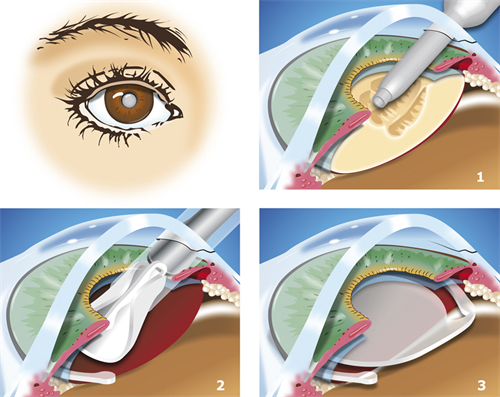

ICL晶体植入手术作为高度近视矫正的主流方案,凭借其可逆性、不损伤角膜的特点,成为越来越多近视患者的选择。

不损伤角膜:适合角膜薄、干眼症等激光手术禁忌人群。

可逆性强:晶体可随时取出,不影响未来其他治疗。

改善比较快:术后24小时即可正常用眼,3天稳定。

视觉质量高:尤其适合较高高度近视(>1000度)患者。